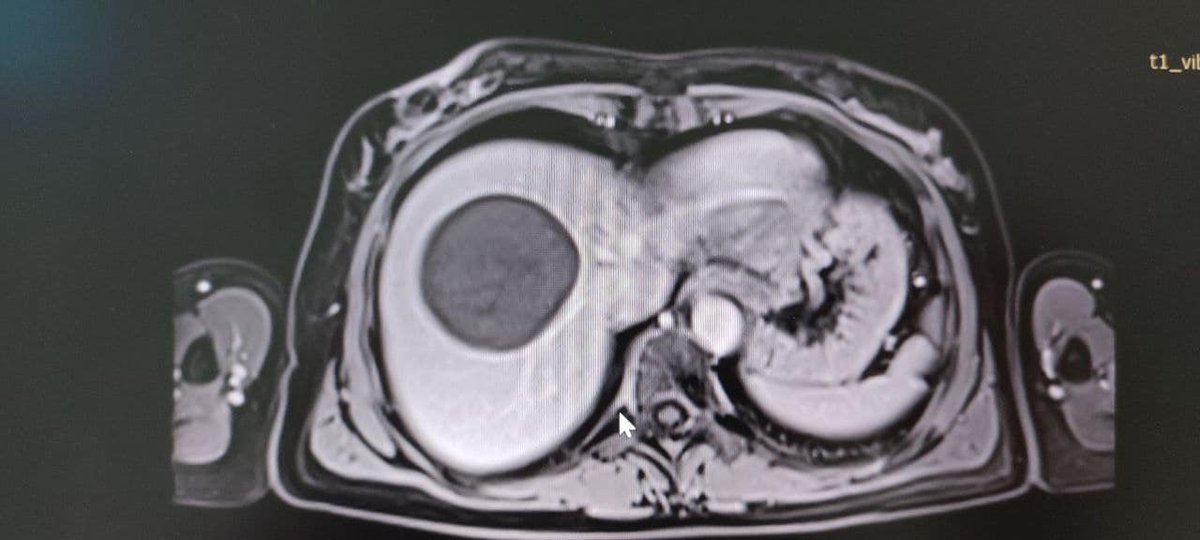

ЩоКіста паразитів у печінці нагадує амніотичний сечовий міхур, в якому дозріває личинки ехінокока. Рак поступово зростає і іноді досягає величезних розмірів (діаметром до 50 см)“, Сказаний У повідомленні. Фахівці Володимир TMO провів операцію та видалив кісту. В даний час у пацієнта все добре.

Прес -служба медичної установи опублікувала фотографію з операційної, але якщо це для вас неприйнятне, не дивіться на вас